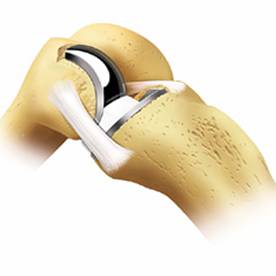

関節の半分の人工関節が片側人工関節(UKA;Unicompartmental Knee Arthroplasty)です。

1990年代まではUKAの長期成績は今ひとつでしたが、2000年以後形や素材が改良され素晴らしい成績となっています。

現在、ジンマー社製UKA Personaを使用しています。変形性膝関節症の中でUKAが適応の場合、TKAよりこちらをお薦めします。手術は85歳まで可能で15~20年持ちます。術後はゴルフ・スキー・ボーリング・ハイキングなどのスポーツももちろん可能です。杖は全く不要となります。